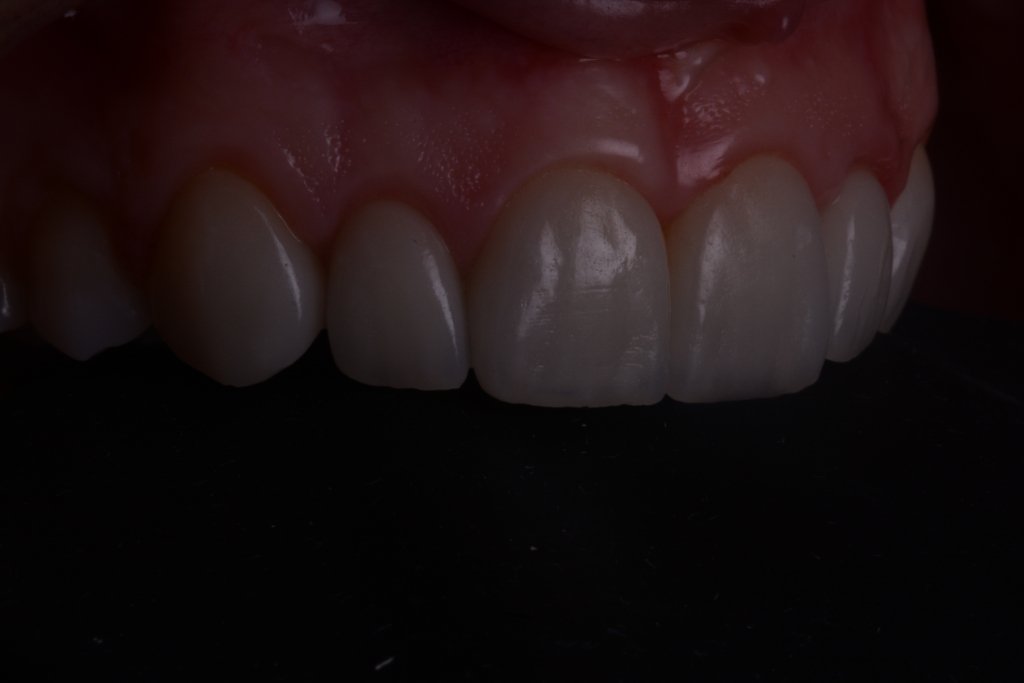

No me asusta esta ligera inflamación, al revés se que están pasando cosas buenas, la encía se esta estabilizando y engordando según los principios de la técnica BOPT. Así que tengo tiempo para disfrutar simplemente del trabajazo de Nacho.

PRONTO LANZARÉ CURSO de tratamiento de la Erupción Pasiva alterada y Carillas BOPT completamente ONLINE